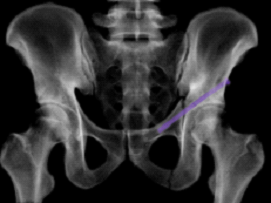

术前医生在数字医学中心工程师帮助下通过CT数据,进行骨盆的三维重建和模拟复位,并进行钉道设计,在虚拟的模型皮肤上进行螺钉进钉点和进钉方向设计。手术中通过这一模型直接和真实的患者进行配准,这样就可以快速地进行体表定位,便于大致确定皮肤切口和钉道方向,然后通过骨科机器人就可以更为精准微创地植入螺钉。

术前将三维模型和患者进行实时匹配

术后X线片和三维CT重建